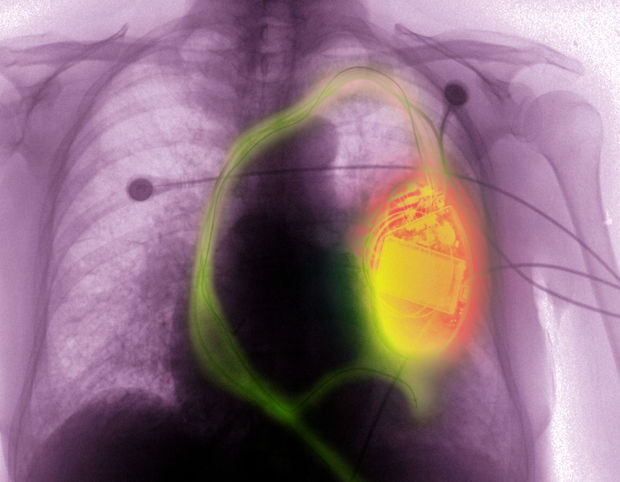

Pacemaker of ingeplante defibrillator en MRI

De auteurs hebben een transversale studie uitgevoerd bij 1.500 patiënten met een MRI-incompatibel toestel (pacemaker n = 1.000 en defibrillator n = 500) bij wie een 1,5 tesla-MRI voor onderzoek buiten de borstkas werd uitgevoerd.

De auteurs concluderen dan ook dat een 1,5 tesla-MRI buiten de thorax geen groot risico inhoudt bij patiënten met een pacemaker of een defibrillator die niet MRI-compatibel is. Voorwaarde is wel dat dezelfde voorzorgsmaatregelen worden genomen als in deze studie.